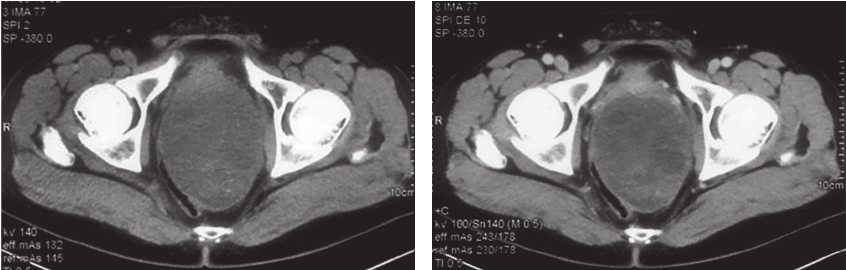

从2017年4月10日起,开始口服甲磺酸伊马替尼400mg/d。服药后每月复查盆腔MRI,示肿瘤无明显变化。考虑患者术前伊马替尼靶向治疗2月余,肿物仍无明显缩小,患者系c-KIT外显子9突变,该型突变对伊马替尼反应欠佳,建议患者增加剂量至600mg/d。患者遵医嘱于2017年6月28日开始加量。伊马替尼加量后2个月复查盆腔MRI,示肿物大小较前仍无显著变化(Choi标准:SD状态)。加做腹盆腔增强CT:盆腔内直肠膀胱窝见一巨大类椭圆形实性肿物,考虑GIST或其他间叶源性肿瘤,肿物边缘光滑,可见包膜,与精囊、前列腺及直肠分界不清,肿物大小约11.7cm×8.9cm,密度欠均匀,内见条片形稍高密度影及散在钙化灶(图2)。

图2 经伊马替尼术前治疗5个月后CT表现